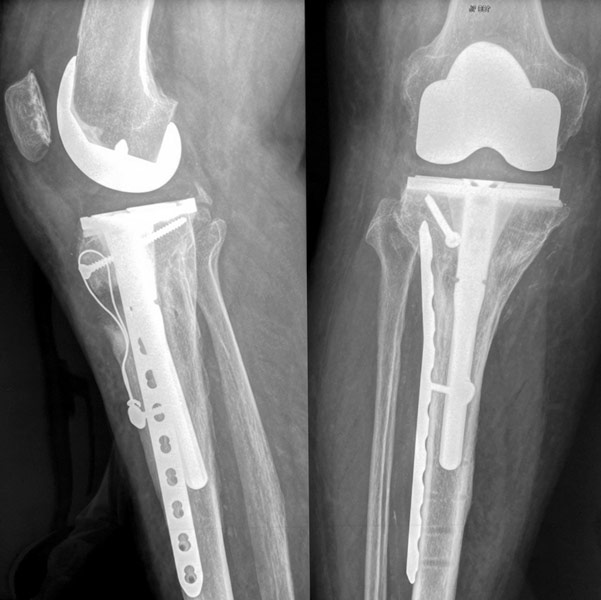

Homme 60 ans, Fracture complexe des 2 plateaux tibiaux opérée par plaques il y a 3 ans. Non consolidation osseuse.

Douleur, raideur.

Reprise par prothèse totale du genou postéro-stabilisée avec tige de reconstruction tibiale et reconstruction de l’appareil extenseur.